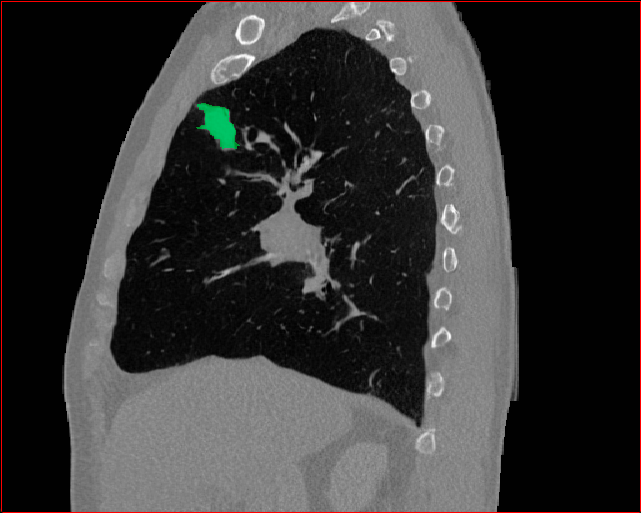

Figure 3 shows the generalizability of MAISI-v2 ControlNet for different body regions and voxel sizes. Figure 4 shows qualitative results for MAISI-v2 ControlNet on 5 types of tumors.

Figure 3: MAISI-v2 segmentation-guided results for small to large volume size and three different regions.

Lung Tumor

0.75×0.75×0.60.75\times 0.75\times 0.6

mm

512×512×512512\times 512\times 512

Figure 4: MAISI-v2 segmentation-guided results for five types of tumors. We show results for different voxel spacing and volume size to demonstrate the flexibility of MAISI-v2. Different Hounsfield Unit window is used to better show the contrast between tumor and normal tissues.